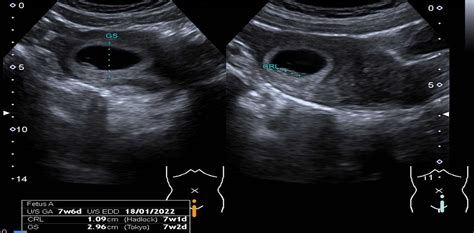

Placenta (plodový koláč) sa začína tvoriť po oplodnení vajíčka v maternici, asi 7 až 10 dní po počatí. Pokračuje v raste počas tehotenstva a funguje ako dôležitý podporný orgán pre dieťa, ale aj matku. Svoj rast začína ako zhluk niekoľkých buniek. V 4. až 5. mesiaci je štandardne plne zrelá a veľká niekoľko centimetrov.